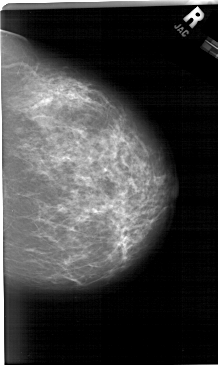

A_1284_1.RIGHT_MLO

LEFT_MLO LINES 6616 PIXELS_PER_LINE 4096 BITS_PER_PIXEL 12 RESOLUTION 43.5 OVERLAY

RIGHT_MLO LINES 6751 PIXELS_PER_LINE 4081 BITS_PER_PIXEL 12 RESOLUTION 43.5 NON_OVERLAY